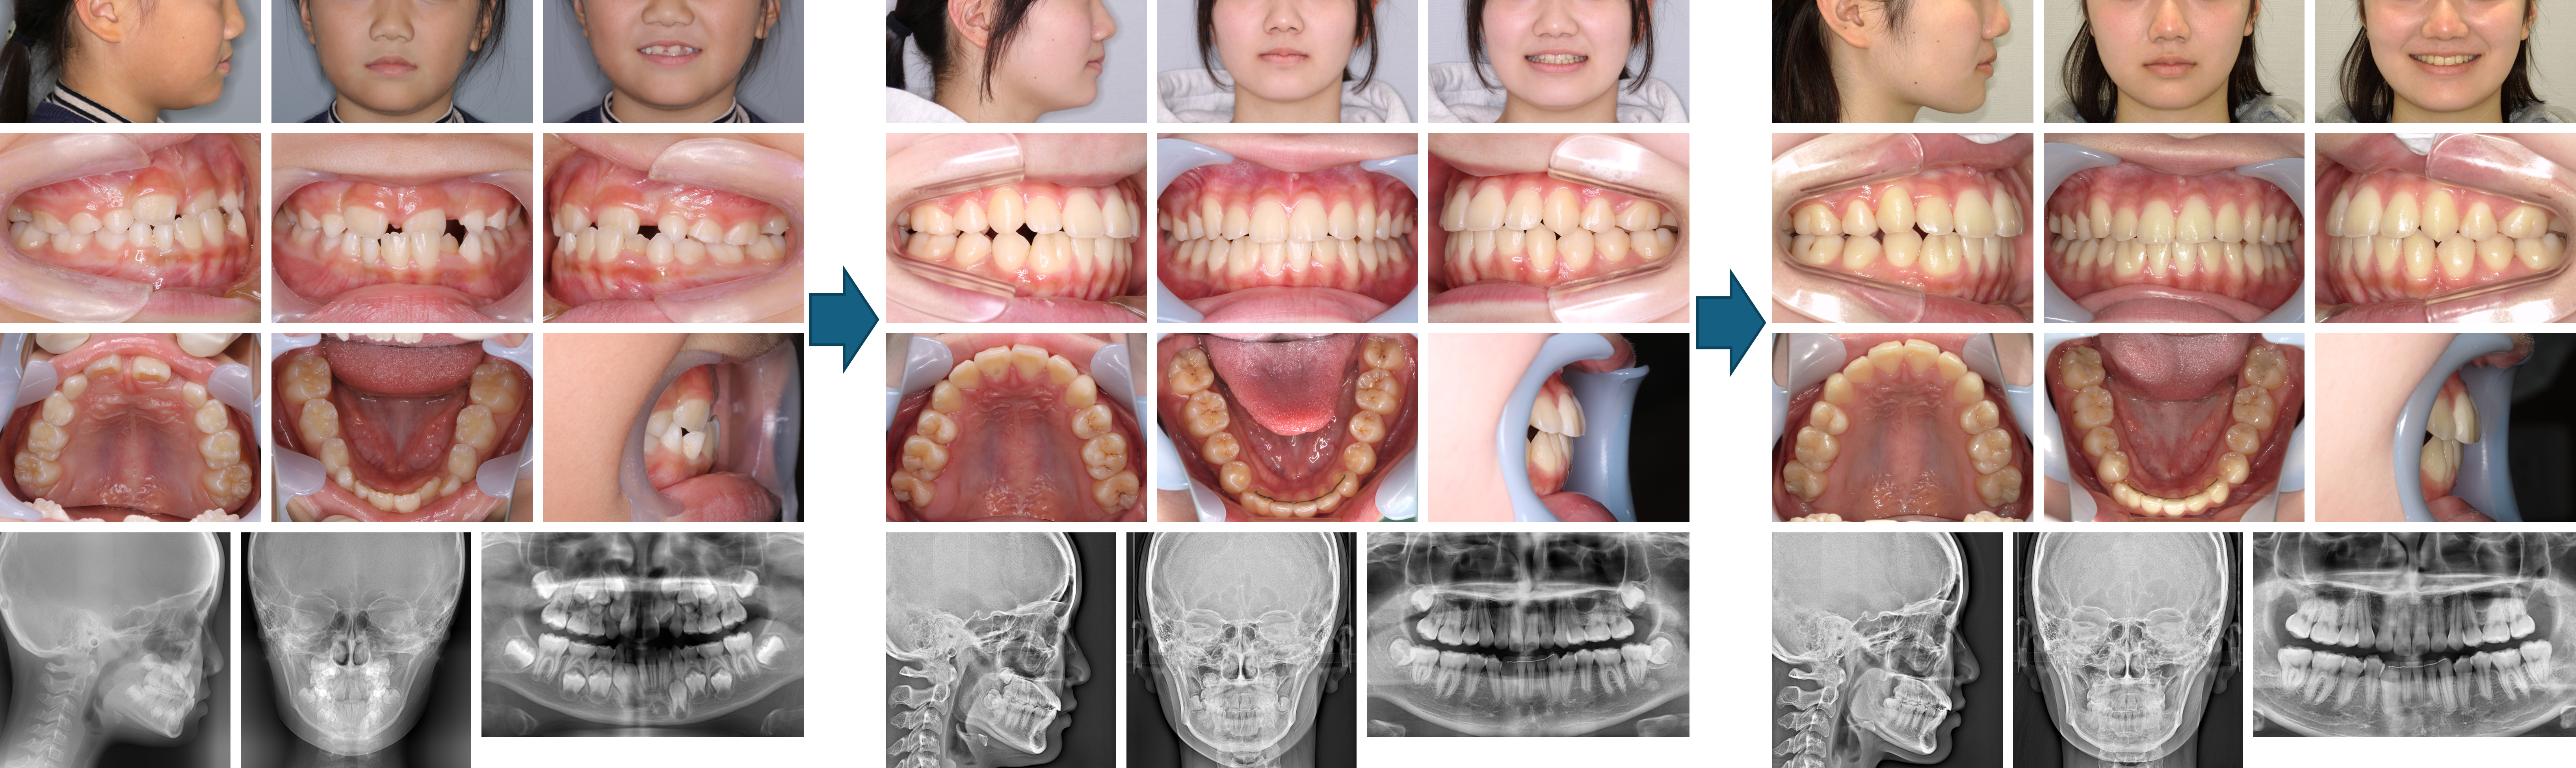

【治療例 K5102】初診時年齢:8歳2か月 / 性別:女性 / 主訴:上の前歯が出ている

治療の概要:下顎骨が後退した著しい上顎前突症例でした。第1期治療では、下顎骨の前方誘導は図るために上顎に咬合斜面板を装着しました。その後、上顎に2×4装置とヘッドギアで上顎骨の成長抑制を図りました。第2期治療では残りの永久歯にマルチブラケット装置を装着しました。その結果、綺麗な側貌と緊密な咬合を獲得できました。

主訴: 上の前歯が出ている

診断名: 上顎中切歯の著しい唇側傾斜を伴う上顎前突

使用した主な装置: サービカルヘッドギア、咬合挙上板、マルチブラケット装置、顎間ゴム

抜歯/非抜歯および抜歯部位: 非抜歯(ただし、乳歯の抜歯はあり)

※上記価格は税込価格です。

※こちらの症例は2009年7月から2019年4月に行った矯正歯科治療ですが、消費税は10%で表示しております。

治療期間:4年7か月

治療回数:66回